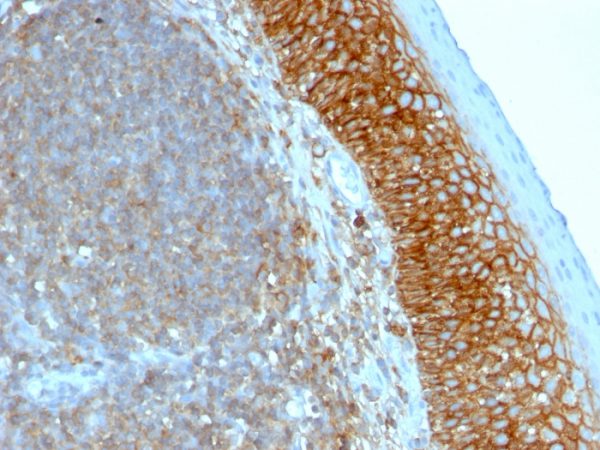

Immunohistochemistry (IHC)

1-2ug/ml

30 min at RT. Staining of formalin-fixed tissues requires heating tissue sections in 10mM Tris with 1mM EDTA, pH 9.0, for 45 min at 95°C followed by cooling at RT for 20 minutes

Recognizes a cell surface glycoprotein of 80-95kDa (CD44) on lymphocytes, monocytes, and granulocytes (Leucocyte Typing Workshop V). Its epitope is resistant to digestion by trypsin and chymotrypsin. This MAb selectively interferes with lymphocyte binding to lymph node, mucosal and synovial endothelium. The CD44 family of glycoproteins exists in a number of variant isoforms, the most common being the standard 85-95kDa or hematopoietic variant (CD44s). Higher molecular weight isoforms are described in epithelial cells (CD44v), which are believed to function in intercellular adhesion and stromal binding. CD44 immunostaining is commonly used for the discrimination of urothelial transitional cell carcinoma in-situ from non-neoplastic changes in the urothelium.

HeLa cells. Paracortex in tonsil or lymph node.